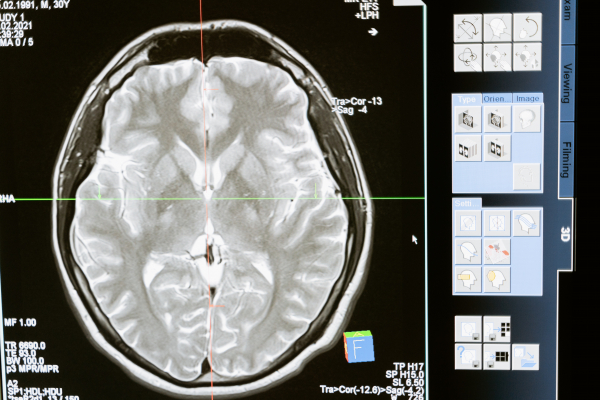

Αγγειακό εγκεφαλικό επεισόδιο παθαίνουν κάθε χρόνο 15 εκατομμύρια άτομα παγκοσμίως και τα 6 εκατομμύρια από αυτούς δεν επιζούν, σύμφωνα με την Παγκόσμια Οργάνωση για τα Αγγειακά Εγκεφαλικά Επεισόδια (ΑΕΕ).